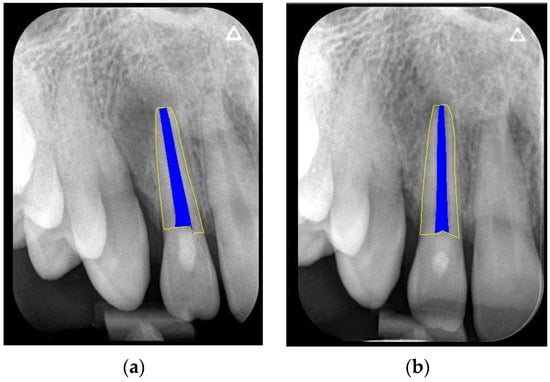

We clinically assessed the outcomes in the absence of any signs and symptoms and a negative cold-sensitivity test. Periapical healing, root elongation, RRA, and apical closure were assessed radiographically (Figure 1a,b). For this, we re-sized the immediate postoperative and follow-up periapical radiographs to match the size and pixels. We used the Freeware Image J software (version 1.47; National Institutes of Health, Bethesda, Rockville, MD, USA) together with the TurboReg plugin tool (Philippe Thevenaz, Biomedical Imaging Group, Swiss Federal Institute of Technology Lausanne, Lausanne, Switzerland) Rasband 1997–2018 [28] as described by Kahler et al. [29]. In brief, for radiographs obtained using different imaging systems, we used the ‘Images to Stack’ and ‘Stack to Images’ functions to equalise the number of pixels in the radiograph. Subsequently, the radiographs of each case were aligned and normalised using the TurboReg plugin tool. This tool enabled the measurement of curved roots (Figure 2a,b). Two evaluators (RY and AYK) conducted the calibration sessions using instructional videos. All cases were separately reviewed by two calibrated examiners. They discussed the case upon obtaining dissimilar results until it was resolved. The above-mentioned changes in root dimension were calculated as a percentage (Figure 3a,b). Hence, we evaluated the effect of the treatment based on the relative increase in RRA and root length.

Figure 3.

The formulae used to calculate relative measurements (%) of the radiographic length (a) and root area (b).

RRA, radiographic root area; REP, regenerative endodontic procedure.

RL0 = the radiographic length at the end of REP and RL1 = the radiographic length at the final follow-up.

RRA0, the radiographic root area at the end of REP, RRA1 = the radiographic root area at the final follow-up of REP.